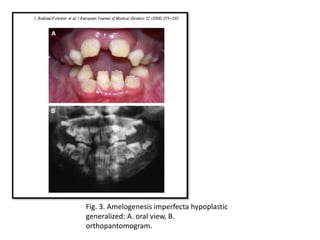

Fig. 3. Amelogenesis imperfecta hypoplastic

generalized: A. oral view, B.

orthopantomogram.

Fig. 3. Amelogenesisimperfecta hypoplastic generalized: A. oral view, B. orthopantomogram.